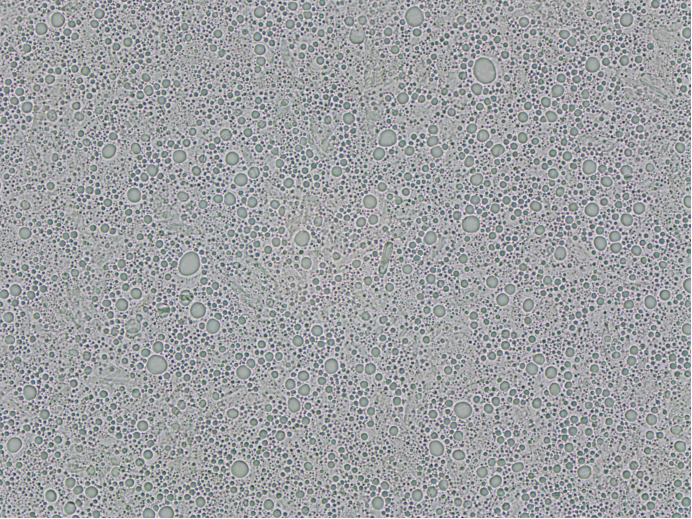

梓夢科技顯微鏡法粒度分析儀ZML310則采用高分辨率光學成像技術,能夠直接捕捉到顆粒的清晰微觀圖像。操作人員通過儀器配備的2000萬像素高清相機,可直觀觀察到顆粒的大小、形狀、表面顏色等細節特征,無論是球形、異形,還是粘連、團聚的顆粒,都能清晰呈現。同時,結合專業的顯微圖像分析軟件,儀器可對顆粒的粒度進行精準測量,包括粒徑、粒徑分布、等效直徑等多項參數。這種 “直觀觀察 + 精準測量” 的模式,實現了粒度與形態的雙重檢測,避免了激光粒度儀因無法識別形態而產生的誤判。在醫藥行業的粒度檢測中,梓夢科技顯微鏡法粒度分析儀ZML310能清晰分辨出不同形態的顆粒狀態,準確測量其粒度,可清晰展示各類形態顆粒的占比情況,為優化制劑工藝提供更全面、可靠的依據。

一方面,該儀器對樣品的分散要求相對較低,無需復雜的前處理流程。對于高黏度的乳膏、軟膏類樣品,只需取少量樣品加在載玻片上,無需稀釋即可直接觀察檢測;對于含有輔料和原料藥多種配比的樣品,可在顯微鏡視野中快速篩選出目標顆粒,排除雜質干擾,確保檢測結果的準確性。

另一方面,針對不均勻混合樣品,梓夢科技顯微鏡法粒度分析儀可通過多點取樣、統計分析的方式,全面掌握樣品的粒度分布情況。例如在混懸液樣品中,可通過在不同區域選取多個觀察點,分別統計各點的顆粒數量及粒徑大小,再通過軟件系統對所有數據進行整合分析,最終得到能夠真實反映整體樣品粒度特征的分布結果,有效避免了因樣品局部不均導致的檢測偏差,解決了激光粒度儀在檢測此類樣品時易出現的“以偏概全”問題。